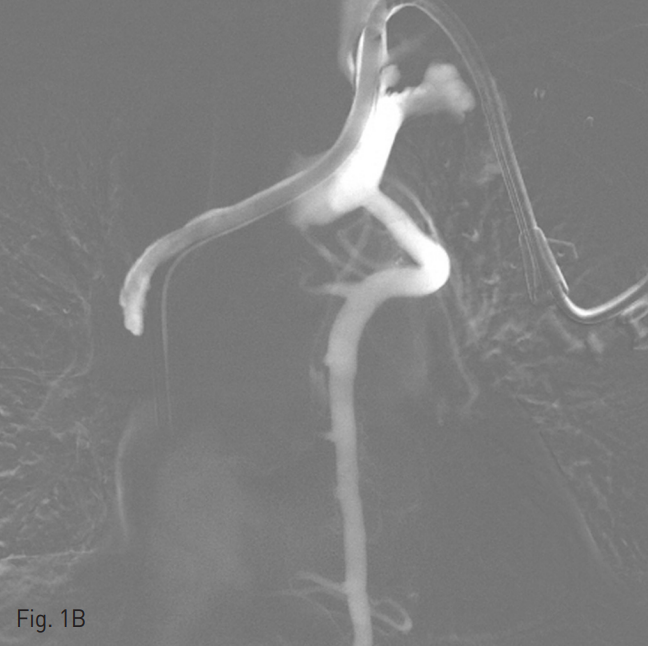

양측 내경정맥을 통한 정맥 조영술에서 상대정맥이 완전히 폐색되어 있으며 (Fig. 1A-B) 이를 대체하기 위해 우측 대퇴정맥에 투석용 카테터를 삽입하였지만 이 또한 10일 후 카테터 주변으로 혈전이 발생하였다(Fig 1C). 이어서 허리 경유 접근을 통해 투석용 카테터 삽입을 위해 하대정맥 천자를 시도하였으며 6 Fr sheath까지 들어간 후에 천자된 곳이 대동맥임을 알게 되어 대동맥에 stent-graft를 넣었다 (Fig. 2A). 투석이 급하여 일단 간정맥을 통하여 투석용 카테터를 삽입하였으나 (Fig. 1D) 이 역시 혈전으로 인한 기능 부전으로 수 차례 교환술을 시행하였다.

Fig. 1. Diffuse venous thrombosis of both internal jugular and femoral veins.

A-B. Venograms via right (A) and left (B) in ternal jugular veins show complete obstruction of superior vena cava with development of collateral flow (A and B).